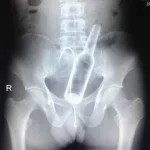

Kazayla Yaşanan Zararlar

- Röntgen filmlerinden “akıl almaz şeyler Hastane koridorlarına düşenler bilir… Doktora görün, tahlilleri yaptır, röntgenleri çektir falan filan derken sayılmadan yaşam gider. Gelin ki bu sefer ilginç şeyler çıkmış ki görün ağzımız açık kaldı